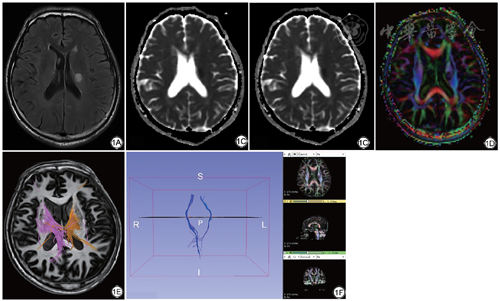

DTT显示梗死灶纤维束直径变细,纤维数量减少,部分断裂,受梗死灶压迫,变形,移位,本研究还通过3D slicer重建锥体束,移动种子点位置多次观察,发现部分患者有少量健侧纤维束通过胼胝体延伸到患侧,有少量纤维束在梗死灶下方偏向患侧延伸(图1)。

采用Extended MR WorkSpace 2.6.3.1工作站对DTI数据进行后处理,重建出表观扩散系数(apparent diffusion coefficient,ADC)图,各向异性系数(fractional anisotropy,FA)图,各向同性图(isotropic image),容积比各向异性(volume ratio aniso)图;分别在放射冠,半卵圆中心,内囊后肢选取感兴趣区ROI。选择感兴趣区后,软件显示相应FA值、ADC值、纤维束数量以及重建后的纤维束图像,使用3D slicer 10.4.2软件进行纤维束重建获得重建图像。